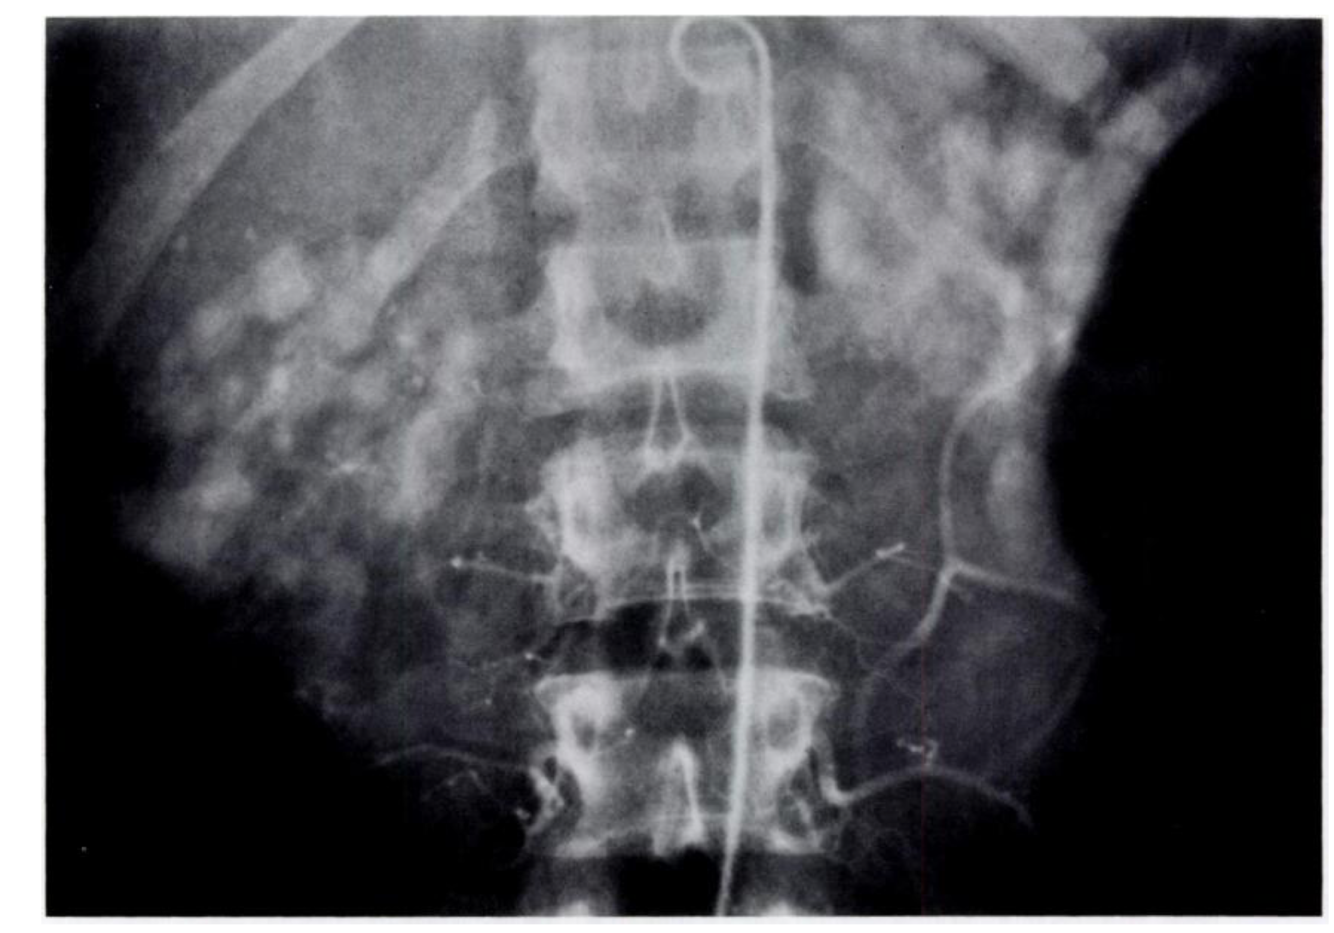

SPOTTED NEPHROGRAM

Figure 5A

A late arterial phase from an aorto- gram shows bilateral spotted neph- rognams in a patient with polyartenitis nodosa.